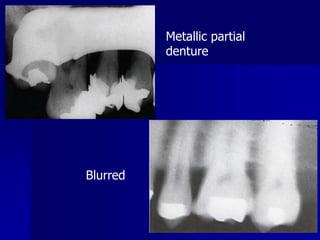

PID alignment artifactTechnique & Projection errorsa. Patient preparation errorRadiopaque artifactDental appliances, body piercings, jewelry & eye glasses left in the mouth during exposure will appear as radiopaque artifact superimposed over the dental image. Correction: all this items should be removed before placing of the film.

Technique & Projection errorsa. Patient preparation errorBlurred imageMovement of the film, patient or X-ray tube head during exposure will result in a blurred image.Correction: the operator should explain for the patient & remind him to remain motionless during exposure.

PID alignment artifactTechnique& Projection errorsa. Patient preparation errorRadiopaque artifactDental appliances, body piercings, jewelry & eye glasses left in the mouth during exposure will appear as radiopaque artifact superimposed over the dental image. Correction: all this items should be removed before placing of the film.

Technique & Projectionerrorsa. Patient preparation errorBlurred imageMovement of the film, patient or X-ray tube head during exposure will result in a blurred image.Correction: the operator should explain for the patient & remind him to remain motionless during exposure.